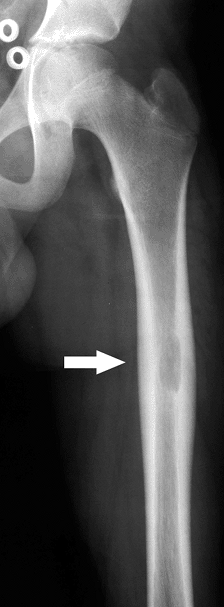

Long bones most commonly affected (Fig. 5.8-3)

Figure 5.8-3 Radiograph of patient with Erdheim-Chester disease showing typical radiographic changes. -